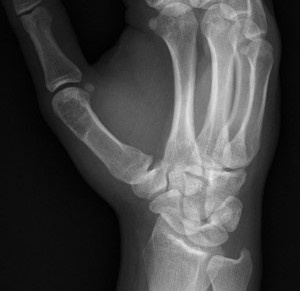

- tubular bones of hand and feet

Hand / Foot

Hand